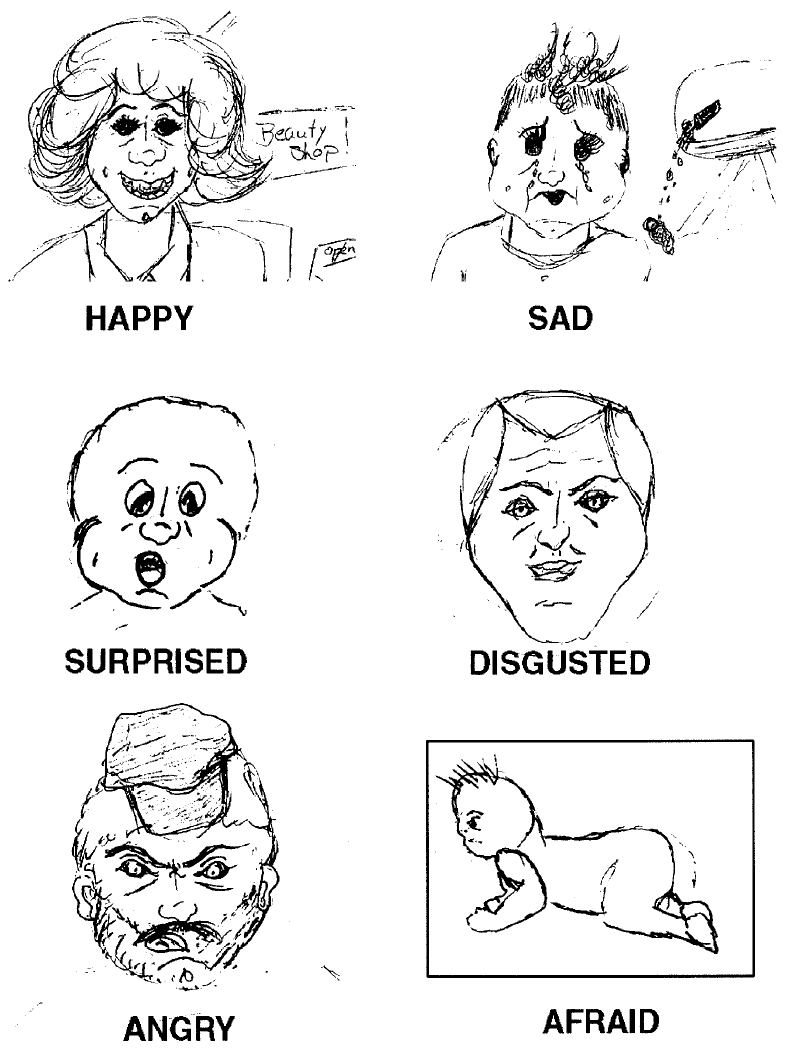

Patients with amygdala damage exhibit diminished emotional fear recognition and expression

Patient S.M. can’t recognize the emotion of fear in photographs. She also exhibits little fear herself (e.g. to dangerous animals, scary houses, films, etc)

Patients with amygdala damage exhibit diminished emotional fear recognition and expression

Note:

Adolphs et al., 1995. Subject with bilateral amygdala lesions was asked to draw facial expressions of emotions.